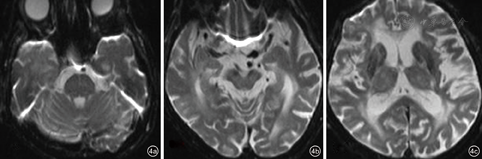

患者,女性,91岁,因"突发反应迟钝伴左侧上下肢无力1 d"入院。患者16 h前出现神智模糊,反应迟钝,活动减少,不愿进食,无呕吐,无二便失禁,无肢体抽搐;2 h前意识障碍加重,伴有头痛、呕吐,遂于安徽医科大学附属合肥医院急诊科就诊,急诊头颅CT提示左侧小脑出血(图1),收入神经内科。患者既往高血压病史多年,不规则服用降压药物,平时监测较少。查体:体温36.8 ℃,血压230/134 mmHg(1 mmHg=0.133 kPa),双肺呼吸音粗,未闻及干湿性啰音,心率100次/min,律齐,偶闻及期前收缩,未闻及杂音。神经系统检查:嗜睡状,问之无应答,额纹对称,双侧瞳孔直径2.5 mm,对光反射存在,双眼右向凝视,左侧上下肢肌张力低,肌力Ⅱ级,右侧上下肢肌力V-级,右侧上下肢肌张力正常,双侧巴氏征未引出。实验室检查:红细胞计数为3.99×1012/L,中性粒细胞计数为15.36×109/L,中性粒细胞百分数83.21%,白细胞计数为18.48×109/L,尿素氮25.50 mmol/L,肌酐382.0 mmol/L,血钾6.15 mmol/L。心电图提示窦性心动过速。头颅CT提示左侧小脑半球出血,双侧侧脑室旁、丘脑、脑桥大片状低密度灶。入院后即刻予以吸氧、心电监护、促醒、脑保护、抑酸护胃、补液支持、脱水降颅压、调节电解质紊乱等治疗,并静脉滴注硝酸甘油以0.25 mg/h调节血压。入院后约14 h患者出现高热达39.9 ℃、呼吸道分泌物明显,意识障碍进一步加重呈中-深度昏迷,考虑肺炎,予以抗炎、化痰、补液、促醒等处理,持续静脉使用硝酸甘油加量至1 mg/h,血压仍持续达(180~200)/(110~120)mmHg,降压治疗效果差,血尿素氮、肌酐进一步恶化。肺部CT提示慢性支气管炎、肺气肿、右肺炎;头颅MR提示双侧侧脑室旁、丘脑、双侧桥脑、中脑广泛T1WI低、等信号,T2WI及FLAIR像呈高信号,弥散加权成像呈低、等信号,表观扩散系数图无信号(图2、图3)。患者于入院后46 h神志转清,血压(120~130)/(80~90)mmHg,左侧肢体肌力恢复至Ⅳ级,要求下床小便,停用硝酸甘油,加用口服非洛地平缓释片5 mg,2次/d,联合厄贝沙坦氢氯噻嗪片1片,1次/d调节血压,余治疗继续予以原方案。半个月后复查头颅MR除小脑出血病灶存留,其余异常信号完全消失(图4)。入院25 d后患者病情稳定,血压120/70 mmHg,可自主进食、正常交流及下床自行活动,予以出院。随访1个月病情无反复。

中央变异型RPLS作为一种特殊类型,其临床预后及特点符合RPLS的特点[9],呈影像学表现重、临床表现轻的特点,及时诊断和治疗后临床症状一般可完全恢复[16]。但如果治疗不及时或不当,也可进一步恶化导致脑出血、梗死或其他不可逆的白质病变。